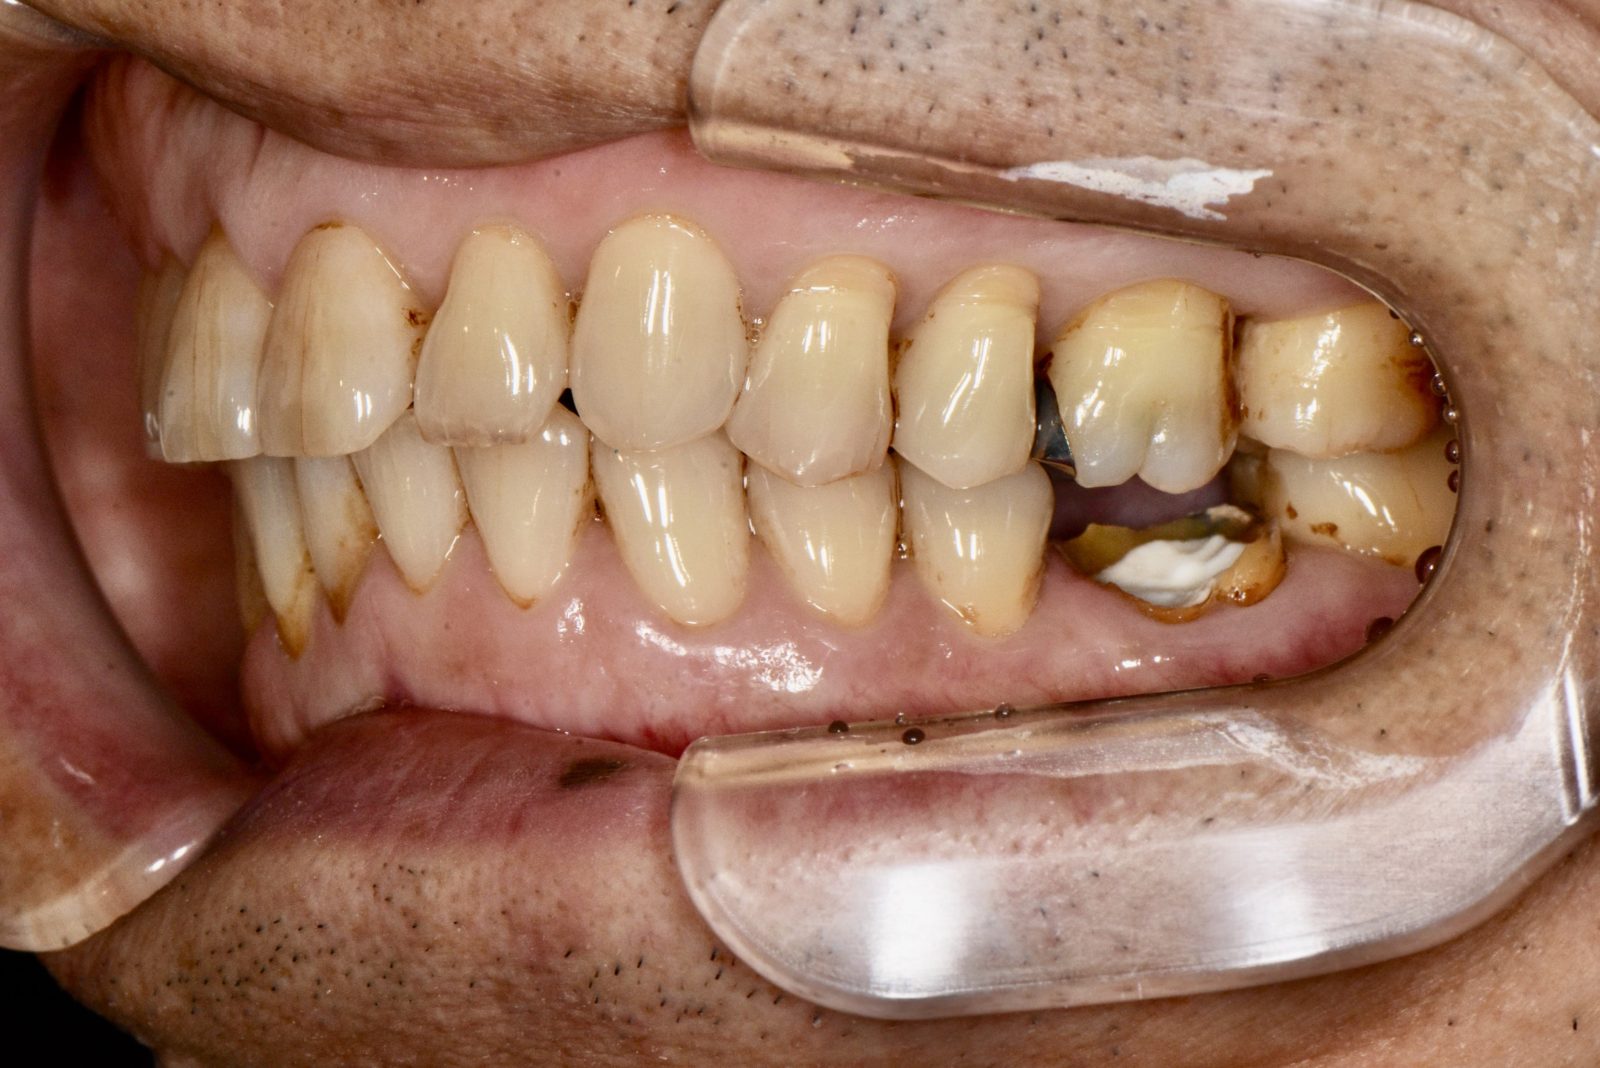

• 治療前

• 治療後

インプラントの技術は日々進歩しており、現在は抜歯した当日に新しい歯を入れることができます抜歯即時荷重と呼ばれているもので、歯を抜いたときにできた穴にそのままインプラントを入れるため、歯茎を切る必要がありません。治療期間が短くなるので、来院回数も少なくできます